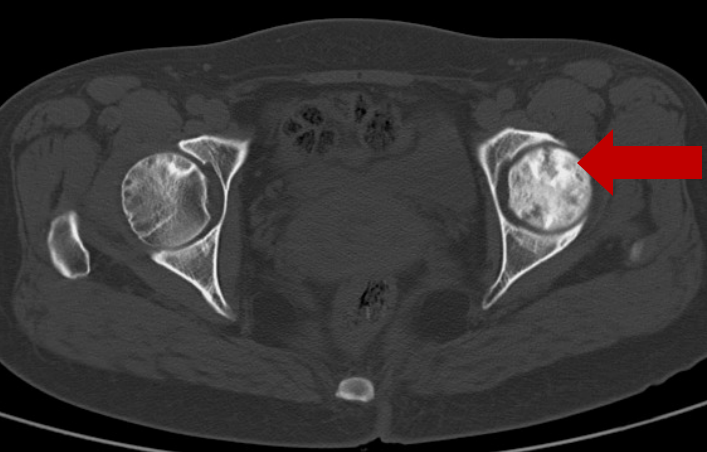

2022年7月11日CT:

左股骨头坏死区缩小,

周围骨质明显生长、修复。

2022年7月复查显示:原股骨头坏死区明显缩小,囊变不明显;关节腔积液、骨髓水肿明显缓解。现无特殊不适,正常生活。